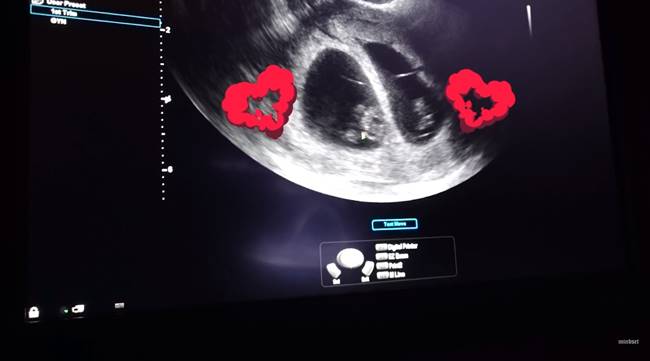

และล่าสุด (14 ตุลาคม 2561) แฟน ๆ เฮกันสนั่น เมื่อ EP นี้ หนุ่มป๊อก เฉลยข่าวดีให้ฟังกันชัด ๆ ว่าไม่ได้มาเพียง 1 เดียว แต่มาเป็นแพ็กคู่ คือได้ลูกฝาแฝดนั่นเอง ซึ่งมีการตรวจดูขนาดของลูกในครรภ์ 8 สัปดาห์ด้วย ซึ่งเบบี๋ทั้ง 2 คน เติบโตตามวัยเป็นอย่างดี โดยทั้งคู่ได้พากันไปดูอุปกรณ์ เสื้อผ้า เตรียมพร้อมรอรับลูก ๆ

ภาพจาก Mindset TV